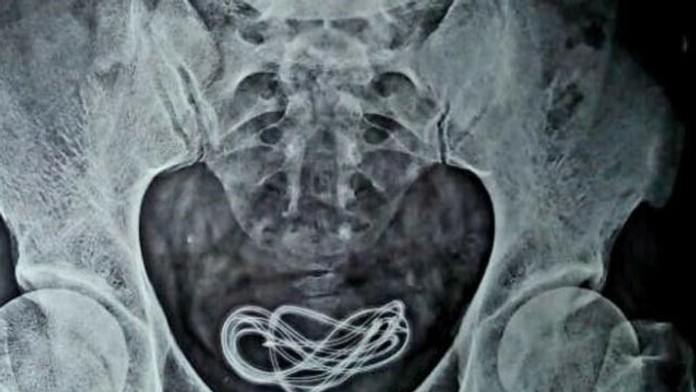

Rozuzlenie prinieslo až röntgenové vyšetrenie. To odhalilo, že muž má v močovom mechúre dvojmetrový kábel, ktorý ležal skrz močovú trubicu, ktorá vedie od penisu k močovému mechúru.